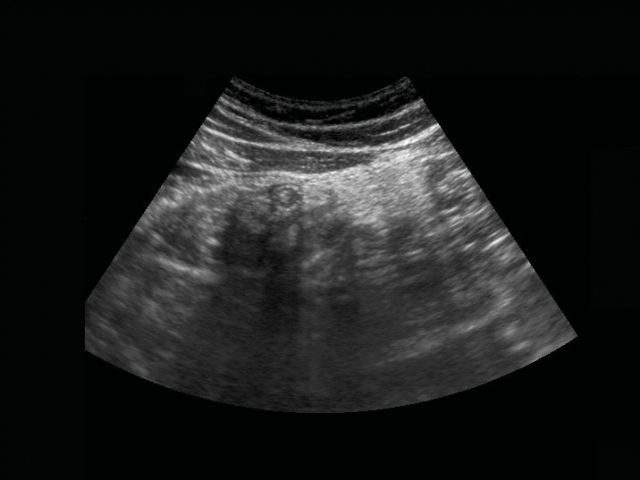

In this pregnant, obese woman, a possible inflamed appendix (arrow with question mark) was visualized during forceful compression deep down in the pelvis.

Subsequent transvaginal US showed a pus-filled, inflamed appendix within 1 cm of the vaginal probe.